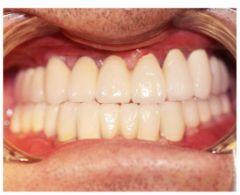

種植修復后照片

通過X光片可以看到,醫(yī)生雖然盡量設計連冠種植,但還是用了十七個植體,盡管已經(jīng)是多次調整后的精簡方案,但手術時長依然長達一天。位老先生之前在另一家醫(yī)院咨詢時,醫(yī)生給的方案是種二十二個植體,光是種植費用就令人大呼“害怕”了。